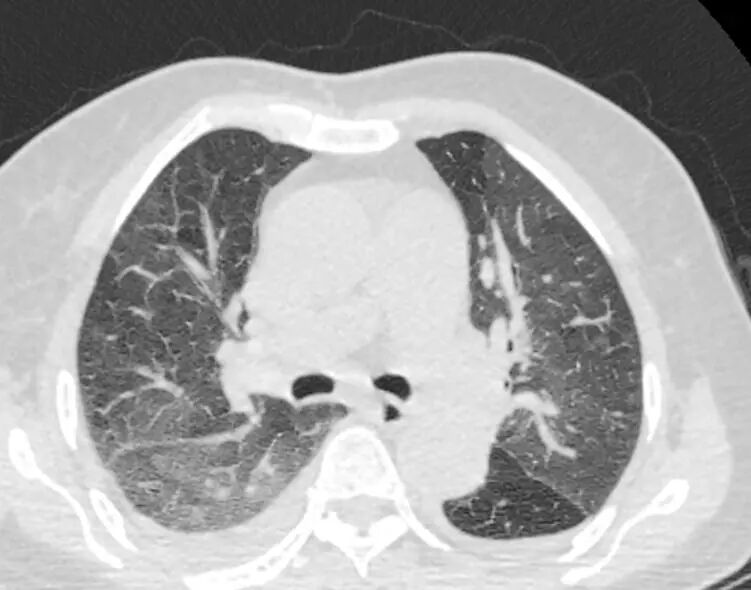

2023-05-06起予DPD方案化疗2程后病情持续进展,血象持续低下,化疗期间反复肺部感染,痰和支气管镜检肺泡灌洗液mNGS多次检出新冠病毒(XBB型)、鲍曼不动杆菌、韦荣球菌、耶氏肺孢子菌、EB病毒等。经积极抗感染后好转。